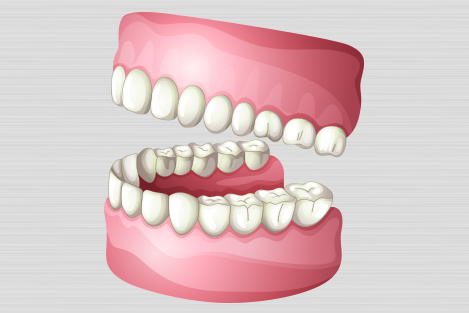

7. Complete dentures

Dentures, also known as false teeth, are prosthetic devices constructed to replace missing teeth; they are supported by the surrounding soft and hard tissues of the oral cavity. Conventional dentures are removable (removable partial denture or complete denture). However, there are many denture designs, some which rely on bonding or clasping onto teeth or dental implants (fixed prosthodontics). There are two main categories of dentures, the distinction being whether they are used to replace missing teeth on the mandibular arch or on the maxillary arch.